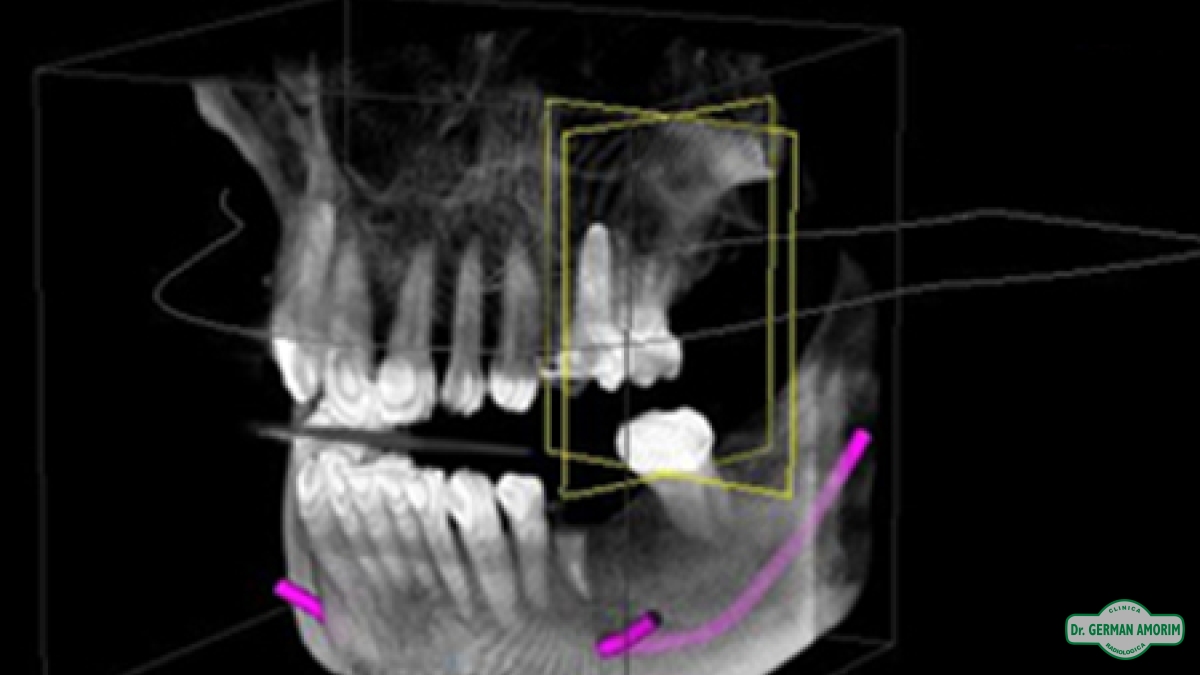

Actualmente y con todos los conocimientos científicos que existen sobre las técnicas implantológicas se recomienda tener siempre una imagen 3D, también en los casos que sea un solo implante. Porque se debe conocer con precisión el espesor de la tabla vestibular para determinar el pronóstico a largo plazo del implante y la única manera de hacerlo es con una tomografía.

En Clínica Amorim contamos con un Tomógrafo de Haz Cónico Orthophos XG de Sirona que mediante la emisión de un haz cónico de rayos genera una serie de imágenes digitales, que son transferidas al computador a partir de las cuales se realiza una reconstrucción en 3D.

El odontólogo utilizando el software específico Galileos puede observar esta imagen en los tres ejes de un espacio tridimensional y trabajar sobre ella para, entre otras cosas, planificar la colocación de los implantes dentales, lesiones ocultas por superposición en las RX convencionales, etc.